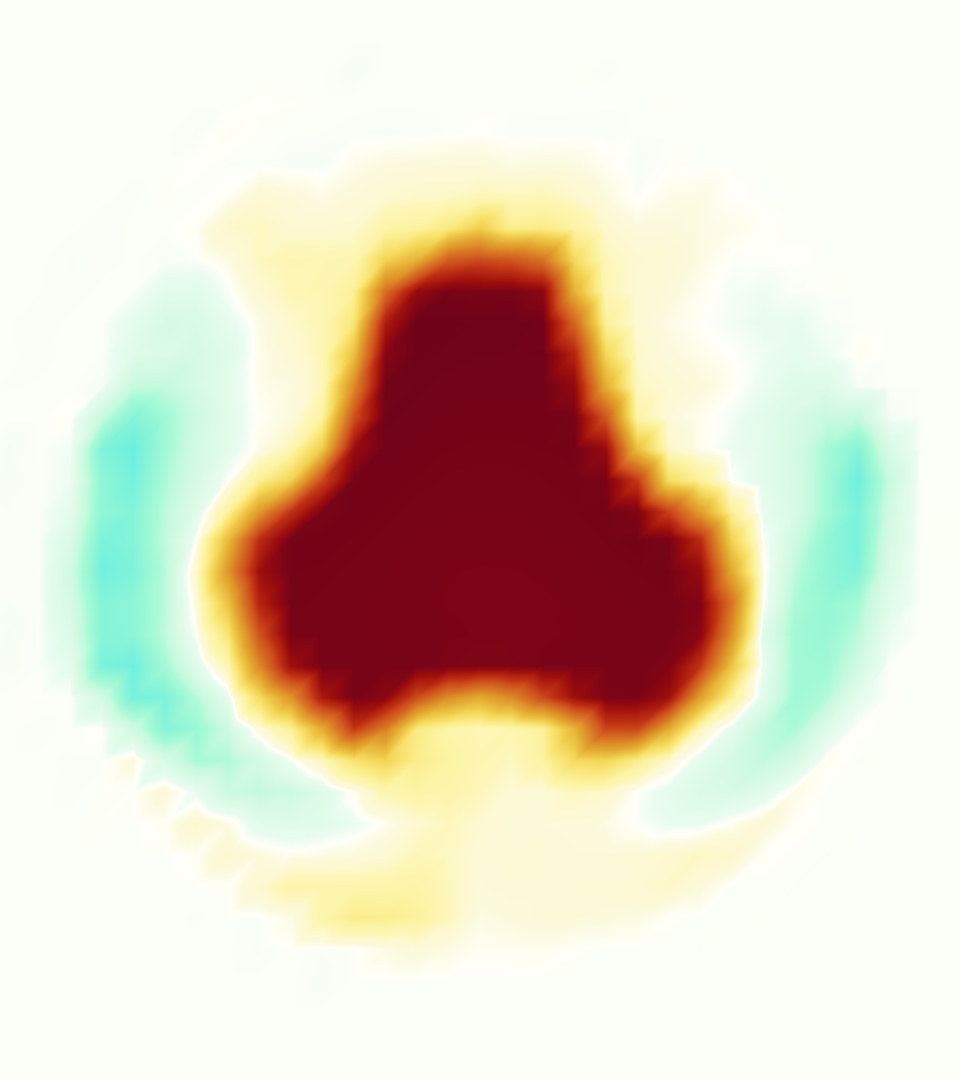

The emergent hemodynamics showed excellent qualitative agreement with experiments. Slice views of the axial component of fluid velocity ( component) in the sagittal plane that cuts through the center of the vessel, parallel to the flow direction, are shown in Figure 5. The flow in both the simulation and the experiment began to accelerate at the same time, with a jet forming through the open valve leaflets. The velocity, angle, and shape of the jet agreed well between the two cases during systole. The simulation captured the slight upward angle of the jet, which was not fully centered in the vessel. It also matched the location where the jet impacts the wall and the slower speed of the jet as it turns with the MPA downstream. As the flow decelerated, the fluid along the interior curve of the vessel reversed first while forward flow persisted where the jet was strongest, as seen in both the simulation and experimental results.

In both the experiment and the simulation, a separation region of reverse flow developed along the interior curve of the vessel under the core jet through the valve. The reverse flow began to develop at the same time in the cardiac cycle and grows throughout systole. The simulation lacked reversed flow in the entire region where reversed flow was present in the experiment, but this region developed some flow separation and had much slower flow than elsewhere in the vessel. Thus, the simulation captured that this is a distinct region from the core jet through the valve opening. There was a smaller amount of slower and slightly reversed flow along the outer curve of the vessel, close to the valve annulus and scaffold support. This region was well-matched between the experiment and the simulation.

Slice views of the (axial) component of fluid velocity in the axial plane, orthogonal to the flow direction, show that the simulation replicated the development of the jet over the cardiac cycle. At each phase, the simulation matched the forward speed of the core of the jet and the locations of reverse flow back towards the valve annulus. While there are some differences in the shape of the jet at certain phases and locations, the simulation clearly produced the general dynamics of the cardiac cycle that are seen in the experiment.

At = 0, the axial slice directly at the valve annulus shown in columns 1 and 2 in Figure 6, there was excellent agreement between the simulation and experiment over the cardiac cycle in the speed and shape of the jet through the valve. In both cases, the axial velocity increased as the flow accelerated during systole and the valve leaflets opened, then decreased during diastole with slight negative velocity before the valve leaflets were fully closed. The forward flow through the valve annulus did not form a full circle, but rather developed a triangular shape with a point of the triangle forming along the interior curve of the vessel, at the bottom of the axial slices. At = 0, the points of this triangular jet shape aligned with the commissures of the valve. This shape persisted during peak systole and was well-matched by the simulation.

The axial slice = 0.625 cm, shown in columns 3 and 4 in Figure 6, cut through the support scaffolding of the valve and the leaflets when they are open. In the experimental data, the shape of the jet changed as it moved downstream. A triangular shape occurred, but the points were then aligned with the middle of each open leaflet as opposed to the commissures. Those points were also more rounded than they were at = 0. The peak velocity of the jet was faster at = 0.625 cm than at = 0, as the flow accelerated through the open valve leaflets. The simulation produced these features at = 0.625 cm. The triangular shape of the jet shifted similarly, and its speed increased compared to the upstream slice. As the flow decelerated into diastole, the jet shape remained roughly triangular but diminished in intensity before disappearing after valve closure.

The jet continued to develop at = 1.25 cm, an axial slice immediately downstream of the valve scaffolding and open leaflets, shown in columns 5 and 6 in Figure 6. In the experimental data, the points of the triangular jet shape extended further towards the vessel wall. In addition, regions of reversed flow developed in the locations downstream of the commissures, resulting in curved sides to the shape of the jet. Each tip of the jet was unique, due to variations in the individual leaflets in the physical bioprosthetic valve. These variations are apparent in the velocity fields, possibly because the jet edges are similar enough cycle to cycle that irregularities are still being captured even with phase averaging. Further discussion of these features can be found in Schiavone et al. [39], which showed that the jet tip shapes occurred in different pulmonary anatomies, demonstrating that they were likely due to inherent properties of each leaflet. The leaflets in the mathematical model of the valve are identical, so these nuances in leaflet variation could not be replicated. The simulation did capture some of the extension of the tips of the jet, as they were closer to vessel wall at slice = 1.25 cm than = 0.625 cm. The curves in the triangular sides of the jet were also present in the simulation, though they were less pronounced than the experimental data. At both = 0.625 cm and = 1.25 cm, the jet shape in the simulation was smoother than the jet in experiment. It is possible that the free edges of the leaflets in the mathematical model are not fully replicating the behavior of the physical leaflets of the bioprosthetic valve, in particular the amplitude or frequency of leaflet flutter, leading to the variations seen in the jet shape at = 1.25 cm downstream of the leaflet edges. The simulation, however, does capture the key features of the triangular shape and speed of the jet. Overall, qualitative comparisons demonstrated that the simulation reproduced key features of the flow during systole and diastole.

A comparison between the phase-averaged velocity resampled onto the MRI grid, the phase-averaged velocity without resampling, the instantaneous flow field without resampling and the MRI velocity field is shown in Figure 8. The coarser resolution is visible as a “stair-stepping” or “pixelated” effect on the phase-averaged resampled velocity, whereas the edges of the jet are more smooth in the phase-averaged velocity with no resampling. Otherwise, the resampled velocity appears qualitatively similar to the phase-averaged velocity with no resampling. Fine scale features were present in the instantaneous field that were lost in the phase-averaging and resampling process. There was more variation in the local velocity of the center of the jet and local areas of high velocity at the edges of the jet that suggested vortices. Vortical structures adjacent to the jet and in the areas of reversed flow were apparent. These comparisons suggest that 4D flow MRI data may lose substantial fine-scale flow features in the flow field via phase-averaging.